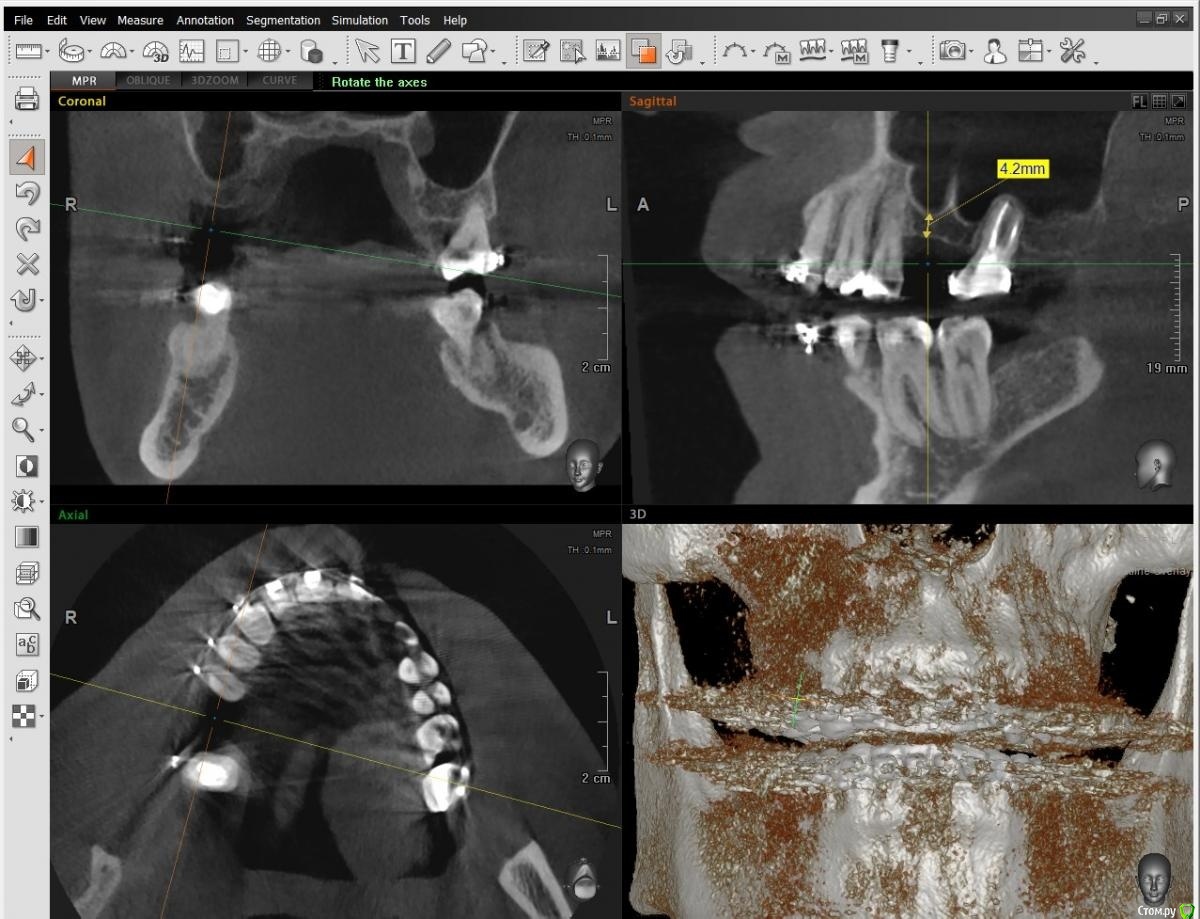

al7777 Опубликовано 10 января, 2021 Поделиться Опубликовано 10 января, 2021 Добрый день.У меня подходит к завершению лечение брекетами и нужно делать имплантацию верхней шестерки справа.Когда касался этого вопроса лет 5 назад, говорили, что нужен открытый синус-лифтинг. Проблема в септе, которая делит место для зуба надвое. Высота кости в этом месте около 4 мм, на снимке видно измерение.Сейчас 2 разных врача предложили сделать закрытый синус-лифтинг.Хотелось узнать мнение уважаемых специалистов с форума по этому поводу. Первый вариант - Установка короткого импланта большого диаметра (5х8 вроде) прямо под септой, синус-лифтинг будет "без применения костнозамещающего материала", имплант Корейский Implantium. Второй вариант от другого доктора- Установка импланта несколько под углом, так чтобы увеличить длину его контакта с костью и выйти с одной стороны от септы. От септы мембрану в пазухе не отслаивать, так как она при этом порвется, а синус-лифтинг сделать закрытым способом, с одной стороны от септы, там где выйдет имплант. Имплант корейский Осстем (можно и Штрауман поставить, но по деньгам сейчас не потяну), плюс пластика мягких тканей. Снимки прикладываю, единственное панорамные снимки сделаны перед установкой брекетов, не смог сейчас сделать панораму с КТ Пикассо. Ссылка на комментарий